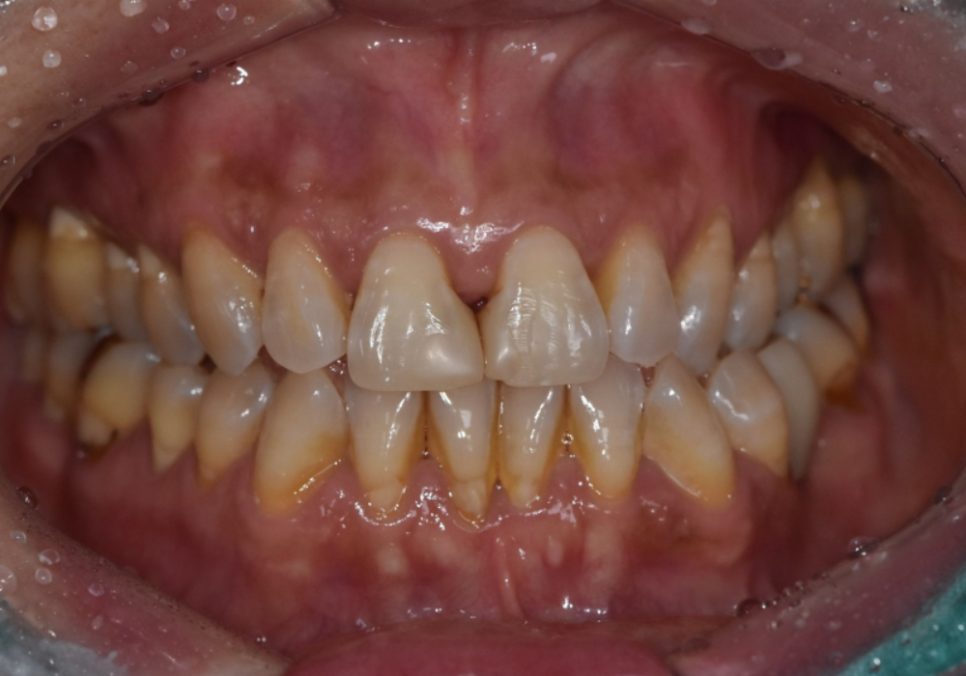

앞니 사이에 음식물이 자꾸 끼고

치아가 누렇게 보이면

대부분은 양치나 관리 부족을

먼저 떠올리게 됩니다.

하지만 실제 치과에서 살펴보면

이런 변화는 단순한 관리 문제라기보다,

나이가 들면서 나타나는

잇몸 높이 변화와

치아 마모가 함께 작용해

생기는 경우가 적지 않습니다.

나이가 들수록 잇몸은

자연스럽게 조금씩 내려가게 되는데,

이 과정에서

잇몸과 레진으로 막아두었던 경계 부위 사이에

미세한 틈이 생기게 됩니다.

잇몸이 내려가면서 치아 사이 공간이

삼각형 모양으로 검게 보이는 현상을

"블랙 트라이앵글(Black triangle)"이라고 합니다.

실제로 1년 전 초진 사진과

최근 사진을 비교해 보니,

잇몸 퇴축이 눈에 띄게 진행되면서

블랙 트라이앵글의 크기가

이전보다 확연히 커진 상태였습니다.